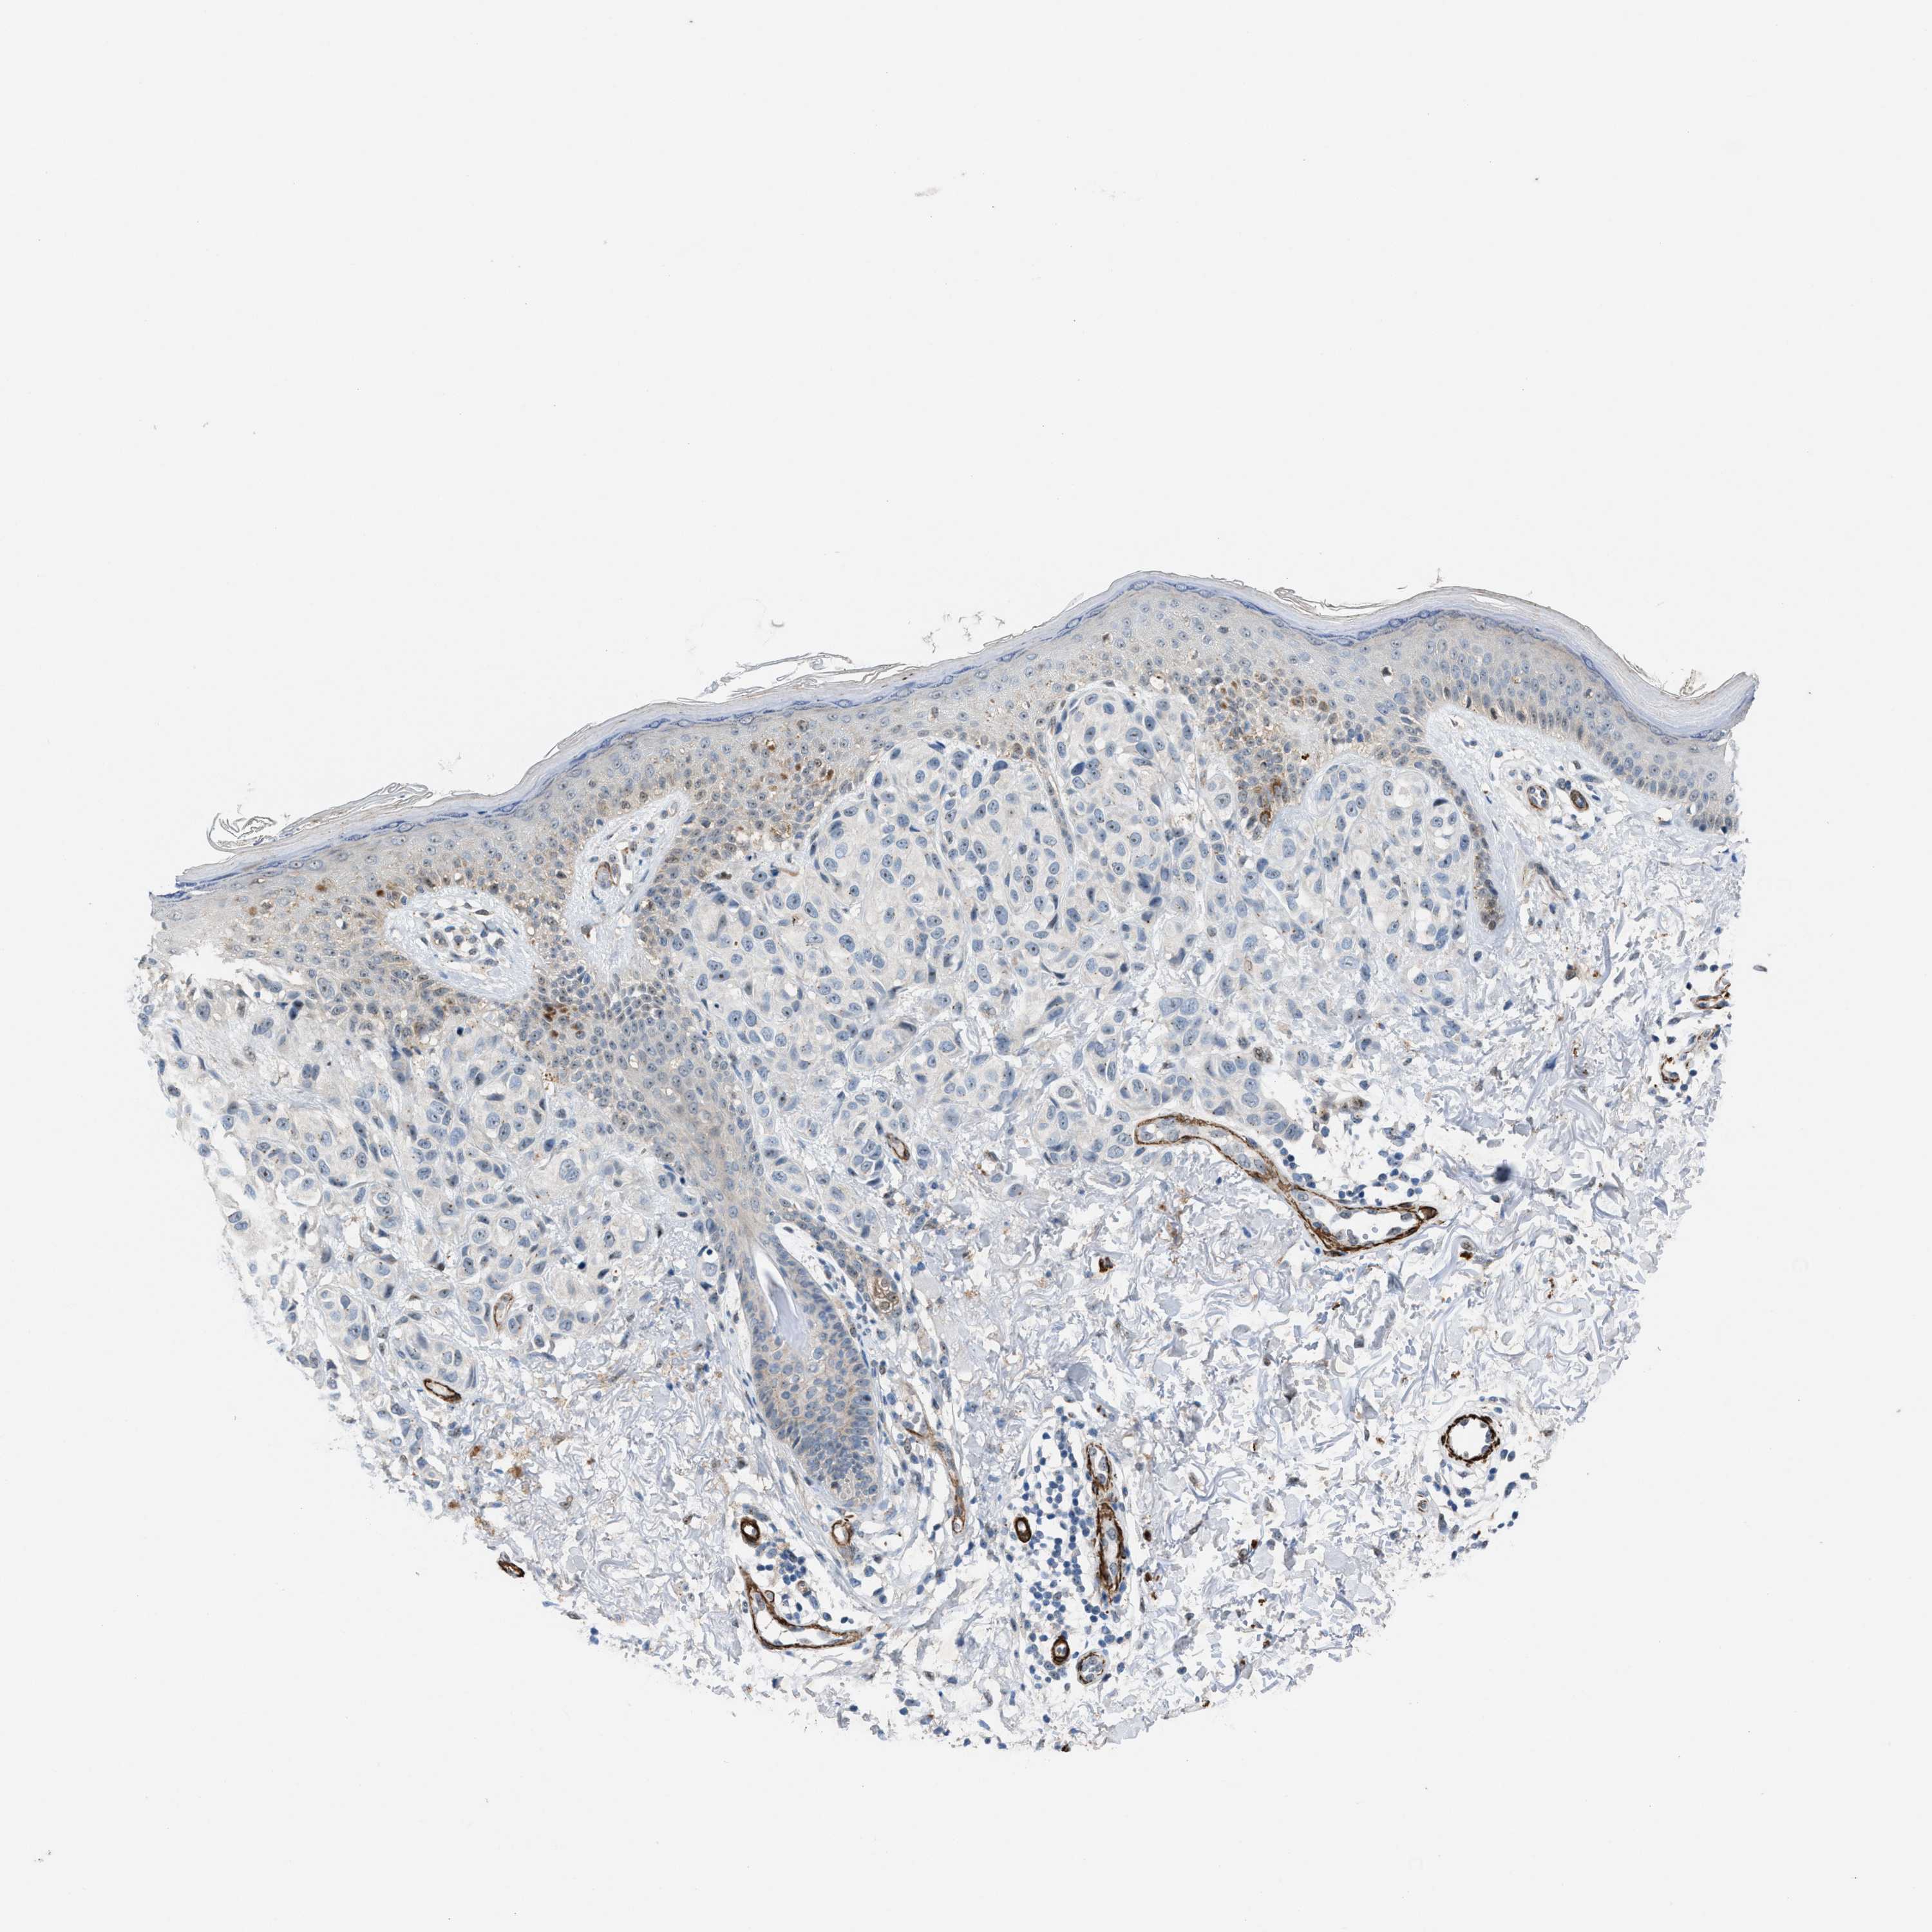

MELANOMA - Protein expressioni

A mouse-over function shows sample information and annotation data. Click on an image to view it in a full screen mode. Samples can be filtered based on level of antibody staining by selecting one or several of the following categories: high, medium, low and not detected. The assay and annotation is described here.

Note that samples used for immunohistochemistry by the Human Protein Atlas do not correspond to samples in the TCGA dataset.

Antibody stainingi

Antibody staining in the annotated cell types in the current human tissue is reported as not detected, low, medium, or high, based on conventional immunohistochemistry profiling in selected tissues. This score is based on the combination of the staining intensity and fraction of stained cells.

Each image is clickable and will lead to virtual microscopy that enables deeper exploration of all samples and also displays staining intensity scores, fraction scores and subcellular localization as well as patient and tissue information for each sample.

Antibody HPA021283

Antibody HPA021332

Staining

High

Medium

Low

Not detected

Intensity

Strong

Moderate

Weak

Negative

Quantity

>75%

75%-25%

<25%

None

Location

Nuclear

Cytoplasmic/membranous

Cytoplasmic/membranous,nuclear

Malignant melanoma, NOS

Malignant melanoma, Metastatic site